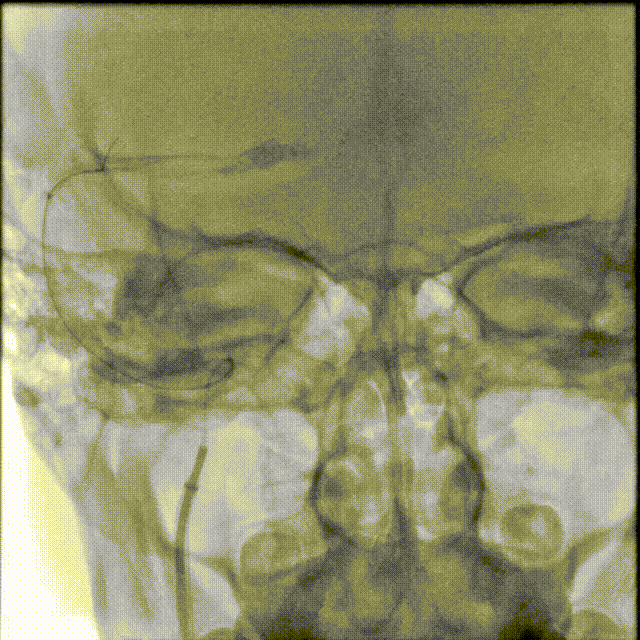

术前CTA/CTP检查,动脉成像未见明显异常,平扫CT可见右侧横窦区域高密度、左侧顶叶片状高密度,窦汇区域、上矢状窦区域高密度充盈。随后紧急性头颅MRV检查,MRV提示上矢状窦及右侧横窦区域不显影。

图注1:1A/1B 平扫CT可见右侧横窦、窦汇区域高密度,额顶叶片状高密度灶

1C 通路CTA检查动脉像未见特殊

1D/1E MRV冠状位及侧位可见上矢状窦及右侧横窦消失,左侧横窦乙状窦部分显影